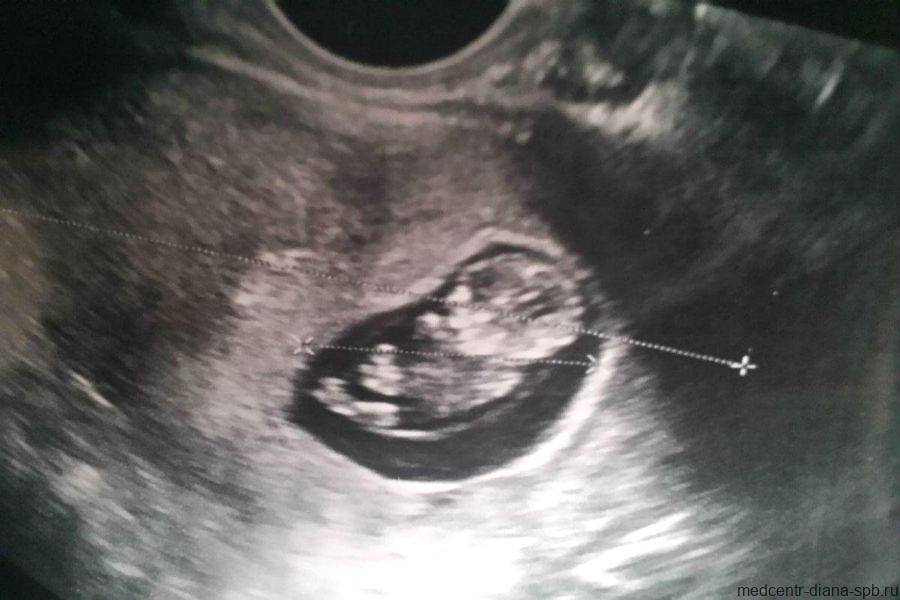

Фото УЗИ ребенка на 12 неделе беременности

Это очень важный период, поскольку гинеколог направляет женщину на первый скрининг. Он включает УЗИ и биохимический анализ венозной крови на гормоны. Ультразвуковое исследование в это время очень информативно и позволяет определить ряд врожденных патологий.

Визуально на фото видны такие особенности плода:

- хорошо просматриваются глаза (они обычно закрыты), нос малыша и другие черты лица;

- ребенок может открывать рот и глотать околоплодные воды;

- размеры плода все еще непропорциональны, но все части тела сформированы;

- в области половых органов происходит гипотрофия мошонки у мальчиков или гипертрофия половых губ у девочек (по этим признакам можно определить пол);

- движения плода хаотичные.

Скрининг на 12 неделе позволяет определить ряд патологий внутриутробного развития. Для этого аппарат УЗИ проводит ряд автоматизированных замеров. На основе этих измерений производят оценку формирования плода.

В этот период обязательно определяют такие параметры:

- длина плода;

- длина бедра;

- окружность живота;

- обхват головы;

- копчико-теменной размер (КТР) – длина от темечка до копчика;

- бипариетальный размер (БПР) – размер от одного виска до другого;

- толщина воротникового пространства;

- объем грудной клетки;

- вес плода (рассчитывается исходя из замеров).

Сопоставить эти данные и выявить патологию может только врач. Если специалист подозревает врожденное заболевание, назначают дополнительный хромосомный анализ.